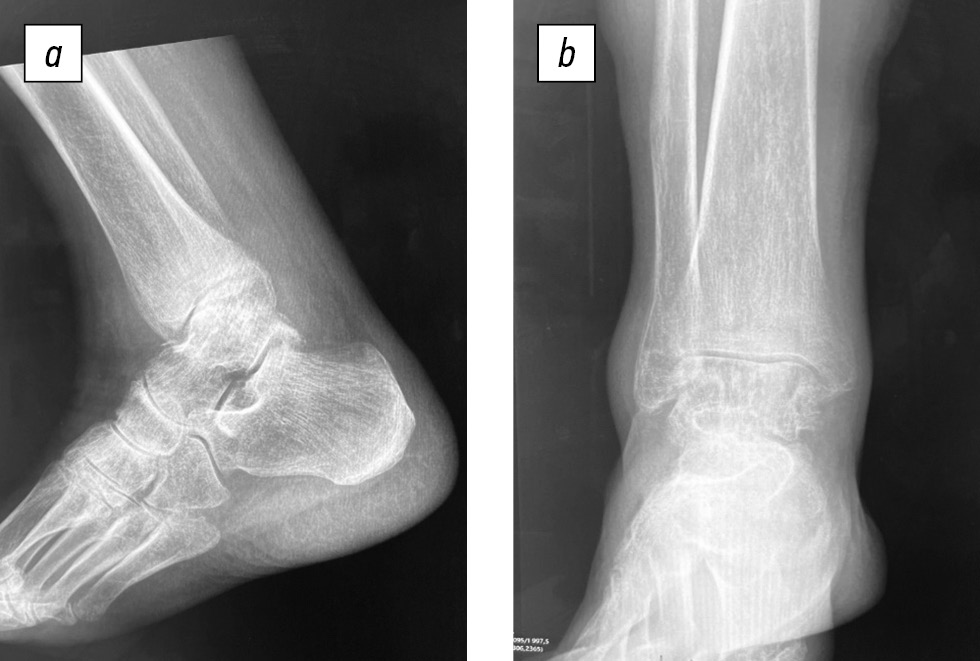

При магнитно-резонансной томографии правого голеностопного сустава: картина стресс-перелома в области метафиза большеберцовой кости. Последствия остеонекроза в виде участков субхондральной кистозной перестройки костной ткани блока таранной кости, ладьевидной, медиальной клиновидной костей (рис. 2).

Рис. 2. Признаки стресс-перелома по ходу метафиза большеберцовой кости в виде неравномерно утолщенной полоски остеосклероза, сопровождающейся небольшим перифокальным межтрабекулярным отеком с выходом на кортикальную пластинку по латеральной поверхности (а, b); c, в блоке таранной кости субхондрально по внутреннему краю отмечены признаки последствий остеонекроза в виде небольшой кистозной перестройки костной ткани диаметром до 3–4 мм с перифокальным остеитом (перифокальным межтрабекулярным отеком) диаметром до 6–7 мм; d, участки субхондральной кистозной перестройки костной ткани и небольшого перифокального отека в ладьевидной кости в области таранно-ладьевидного сочленения. STIR — инверсия-восстановление спинового эха; PD FS — протонная плотность с подавлением жира.

Fig. 2. Evidence of a stress fracture along the tibial metaphysis with a heterogeneously thickened osteosclerotic band with a mild intertrabecular edema involving the cortical plate along the lateral aspect (a, b); c, the trochlea of the talus shows signs of osteonecrotic sequelae in the subchondral region along the medial margin, as evidenced by a mild cystic lesion in the bone tissue up to 3–4 mm in diameter with perifocal osteitis (perifocal intertrabecular edema) up to 6–7 mm in diameter; d, subchondral cystic lesions in the bone tissue and mild perifocal edema in the scaphoid bone in the area of the astragaloscaphoid joint. STIR, short tau inversion recovery; PD-FS, fat-saturated proton density.